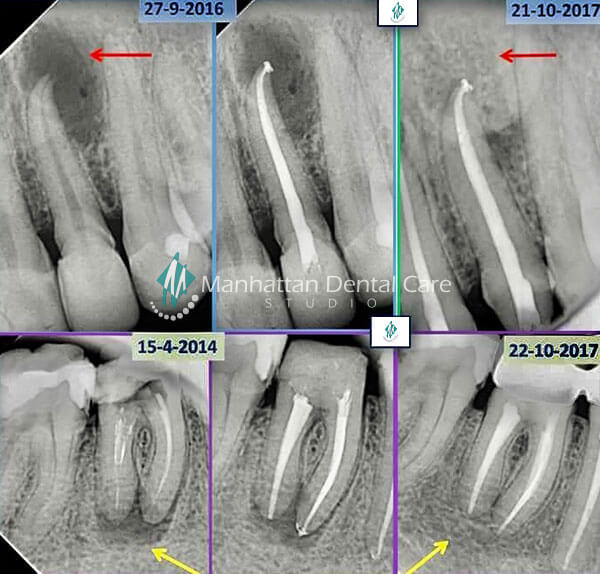

The inside of each tooth is filled with soft tissue known as pulp, which is made up of blood vessels and nerves and serves to keep the tooth alive. Cavities, injuries or trauma, cracks or repeated dental work can compromise the tooth’s outer layers and leave the pulp vulnerable to infection. Root canal therapy involves clearing away the infected or damaged tissue, bacteria and any decay, cleansing the chamber and root canal, filling the space and then sealing the tooth to prevent any further damage. Typically, we’ll place a crown over the tooth to protect it and restore your smile. In the vast majority of cases, with good oral hygiene and regular dental visits, treatment will last a lifetime.